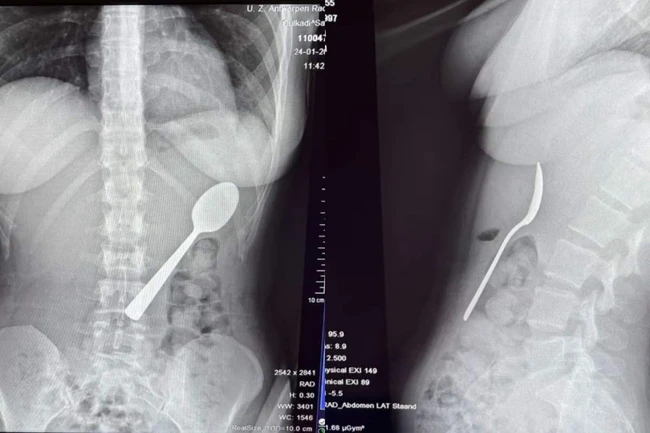

O femeie de 28 de ani din Belgia a trăit momente terifiante după ce a înghițit accidental o lingură de 17 centimetri. Incidentul s-a produs în timp ce mânca iaurt pe canapea, iar totul a pornit de la o reacție neașteptată a câinelui ei, un energic Hungarian Vizsla pe nume Marley.

O femeie din Belgia a înghițit o lingură FOTO: Jam Press

Medicii au decis să îi îndepărteze lingura sub anestezie locală FOTO: Jam Press

Medicii au decis să îi îndepărteze lingura sub anestezie locală, evitând o operație deschisă. Procedura a fost delicată, necesitând rotirea lingurii în interiorul stomacului pentru a putea fi extrasă în siguranță.